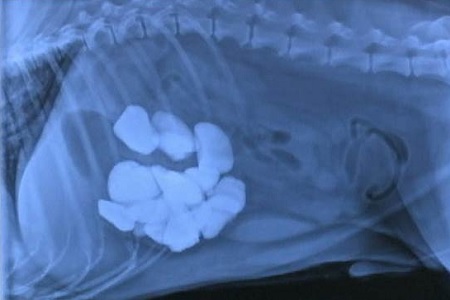

Costipazione e blocco intestinale: un oggetto o un agglomerato di lettiera possono rimanere incastrati a lungo nell’intestino, impedendo al cibo e alle feci di passare. Un’occlusione intestinale è un problema molto grave, che spesso richiede un intervento chirurgico d’urgenza. Ancora più particolare è il rischio legato all’ingestione di gomitoli di lana, spago e lacci: questi possono “agganciarsi” in un punto dell’intestino, che finisce così per attorcigliarsi su se stesso;

Lacerazione e perforazione di stomaco e intestino: un oggetto appuntito o una pietra possono facilmente creare dei tagli anche piuttosto profondi in qualunque punto dell’apparato digerente, dalla bocca fino all’ano. Nei casi più gravi possono addirittura forarne completamente le pareti, provocando emorragie e gravi infezioni;